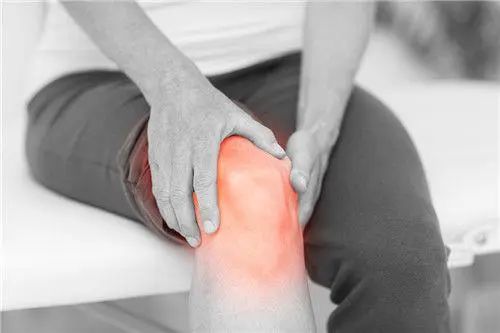

一旦患上关节炎

身体会出现红、肿、热、痛等问题

严重会导致关节畸形(致残率高达53%)

最终劳动能力丧失,生活无法自理

晚年只能在轮椅上度过